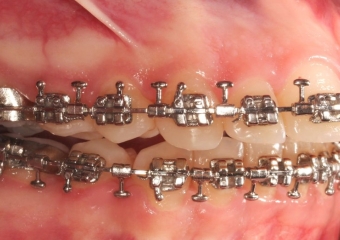

Mordida inicial

Mordida após a cirurgia